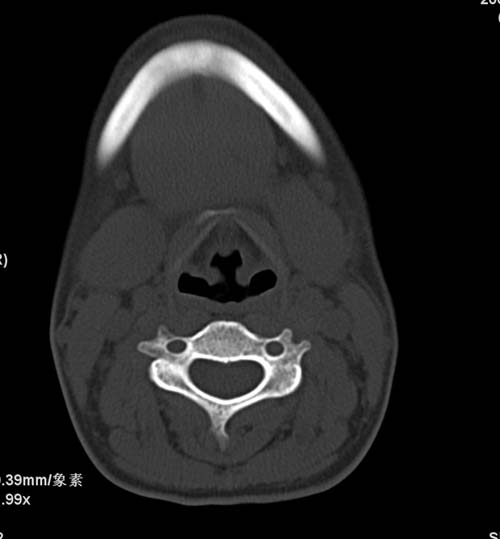

标题: CT22662:女 23 自述双侧颌下腺肿大年余 近来疼痛 左侧明显 [打印本页]

标题: CT22662:女 23 自述双侧颌下腺肿大年余 近来疼痛 左侧明显

见双侧颌下腺略肿大  未见结石及钙化 考虑双侧慢性炎症 ?请指教